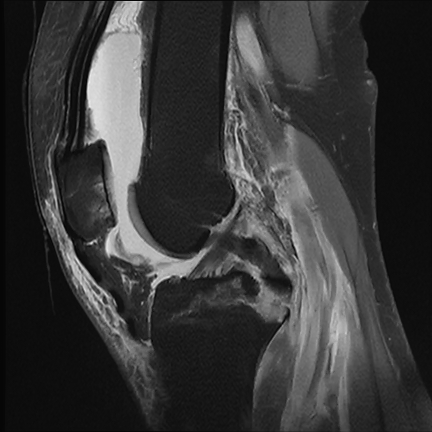

▲术后X片提示膝关节交叉韧带止点撕脱骨折

已复位、固定